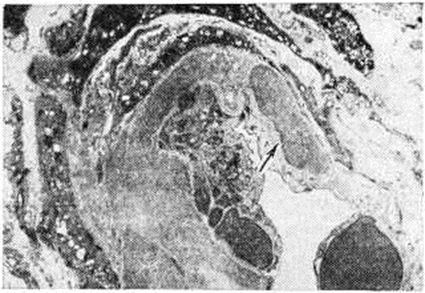

Доброкачественная форма характеризуется артериолосклерозом (рисунок 1), нередко в сочетании с атеросклерозом почечной артерии и её крупных ветвей, атрофическими изменениями групп нефронов с вторичным гиалинозом клубочков (рисунок 2), увеличением соединительнотканной стромы, гиалинозом сосочков пирамид. Макроскопически поверхность почек мелкозернистая, а при сочетании с атеросклерозом — крупнобугристая. По мере нарастания артериолосклеротических изменений, сочетающих плазморрагию (смотри полный свод знаний) и гиалиноз (смотри полный свод знаний), и выключения новых групп нефронов развивается почечная недостаточность (смотри полный свод знаний). Злокачественной форме свойственны фибриноидный некроз артериол (артериолонекроз) и капиллярных петель клубочков (рисунок 3, а), отёк стромы, кровоизлияния, белковая дистрофия эпителия канальцев. Очень быстро в ответ на некротические изменения развивается склероз почек (рисунок 3, б). Подобные изменения могут возникать и при эклампсии (злокачественный постэкламитический Нефросклероз).